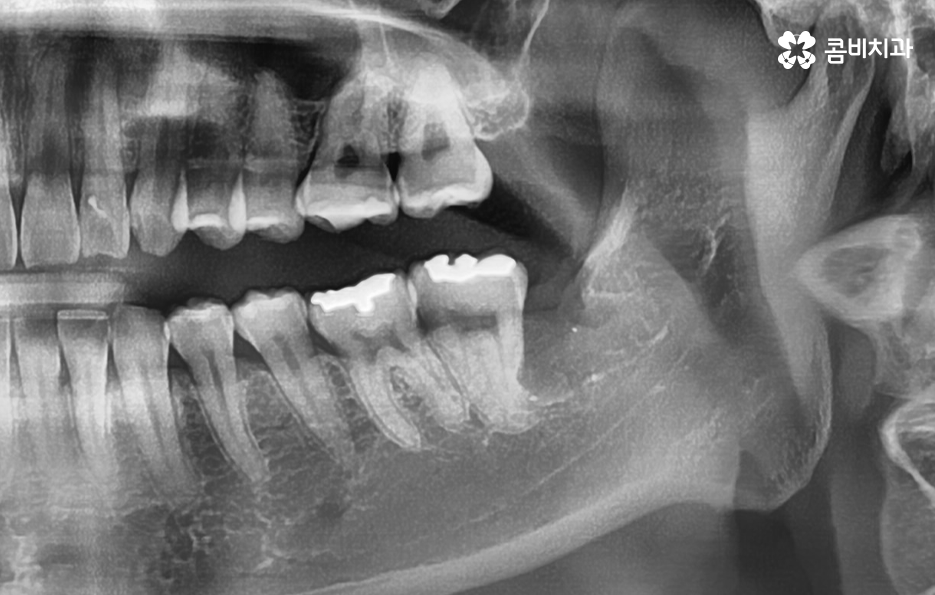

위 사례 이미지의 경우 그래도 다행인 점은 사랑니 발치 시점이 늦지 않아서 완전 누운 사랑니 임에도 큰 고생은 안했던 사례라고 본다면 아래 환자분의 사례는 이미 사랑니 뿐 아니라 어금니 까지 충치가 심해진 사례라고 할 수 있는데요

위 사례 이미지의 경우 사랑니가 누워 있는 정도는 덜하지만 사랑니 발치 시점이 늦어져서 사랑니와 인접 치아 모두 충치가 심해진 사례라고 할 수 있어요

사랑니 발치로 고생했던 분들의 사례를 살펴보면 발치 자체를 미루다가 사랑니 발치도 어려워지고 어금니도 함께 치료해야 하면서 치료비 뿐 아니라 자연치아의 손상이 커지는 경우가 대표적이며 사랑니로 인한 문제는 충치 뿐 아니라 사랑니와 어금니 사이 치조골이 녹아 내리면서 치주염이 심각해지는 경우도 많기 때문에 잇몸 건강에 대한 부분도 고려하실 필요가 있어요